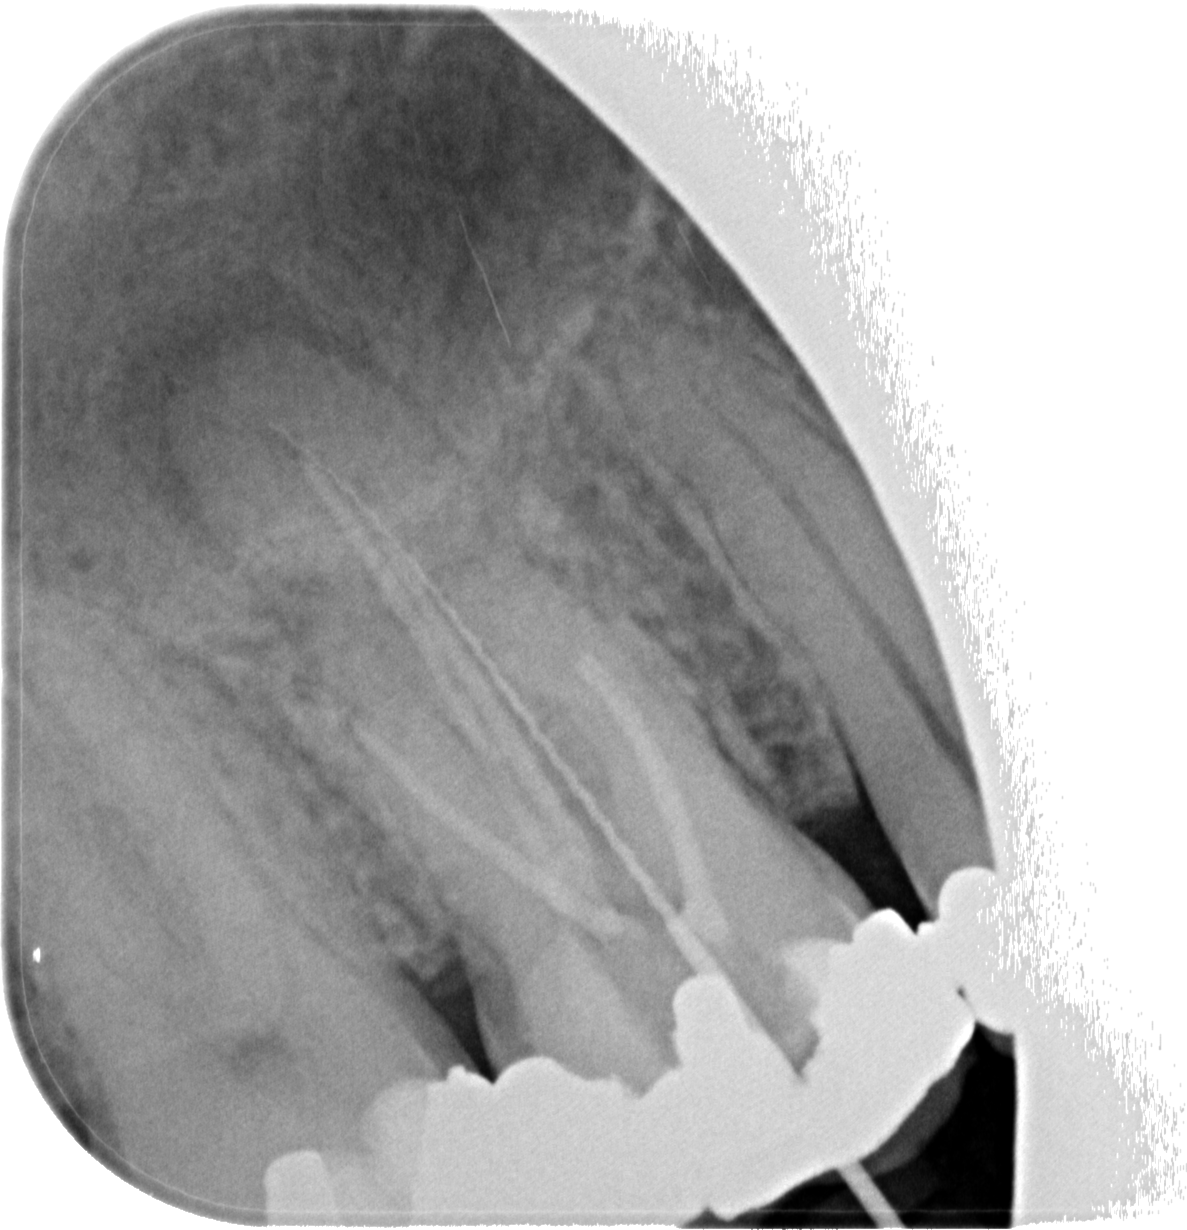

• dent. Aufbau

• 4 Wurzelkanäle

• Wurzelkanalbehandlung Zahn 16

• mit Revision